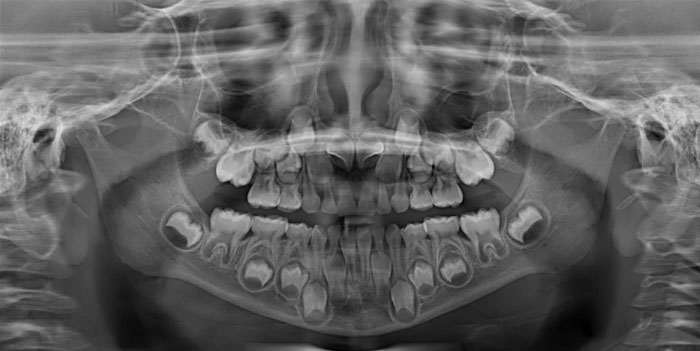

Гипердонтия — заболевание, связанное с лишними зубами